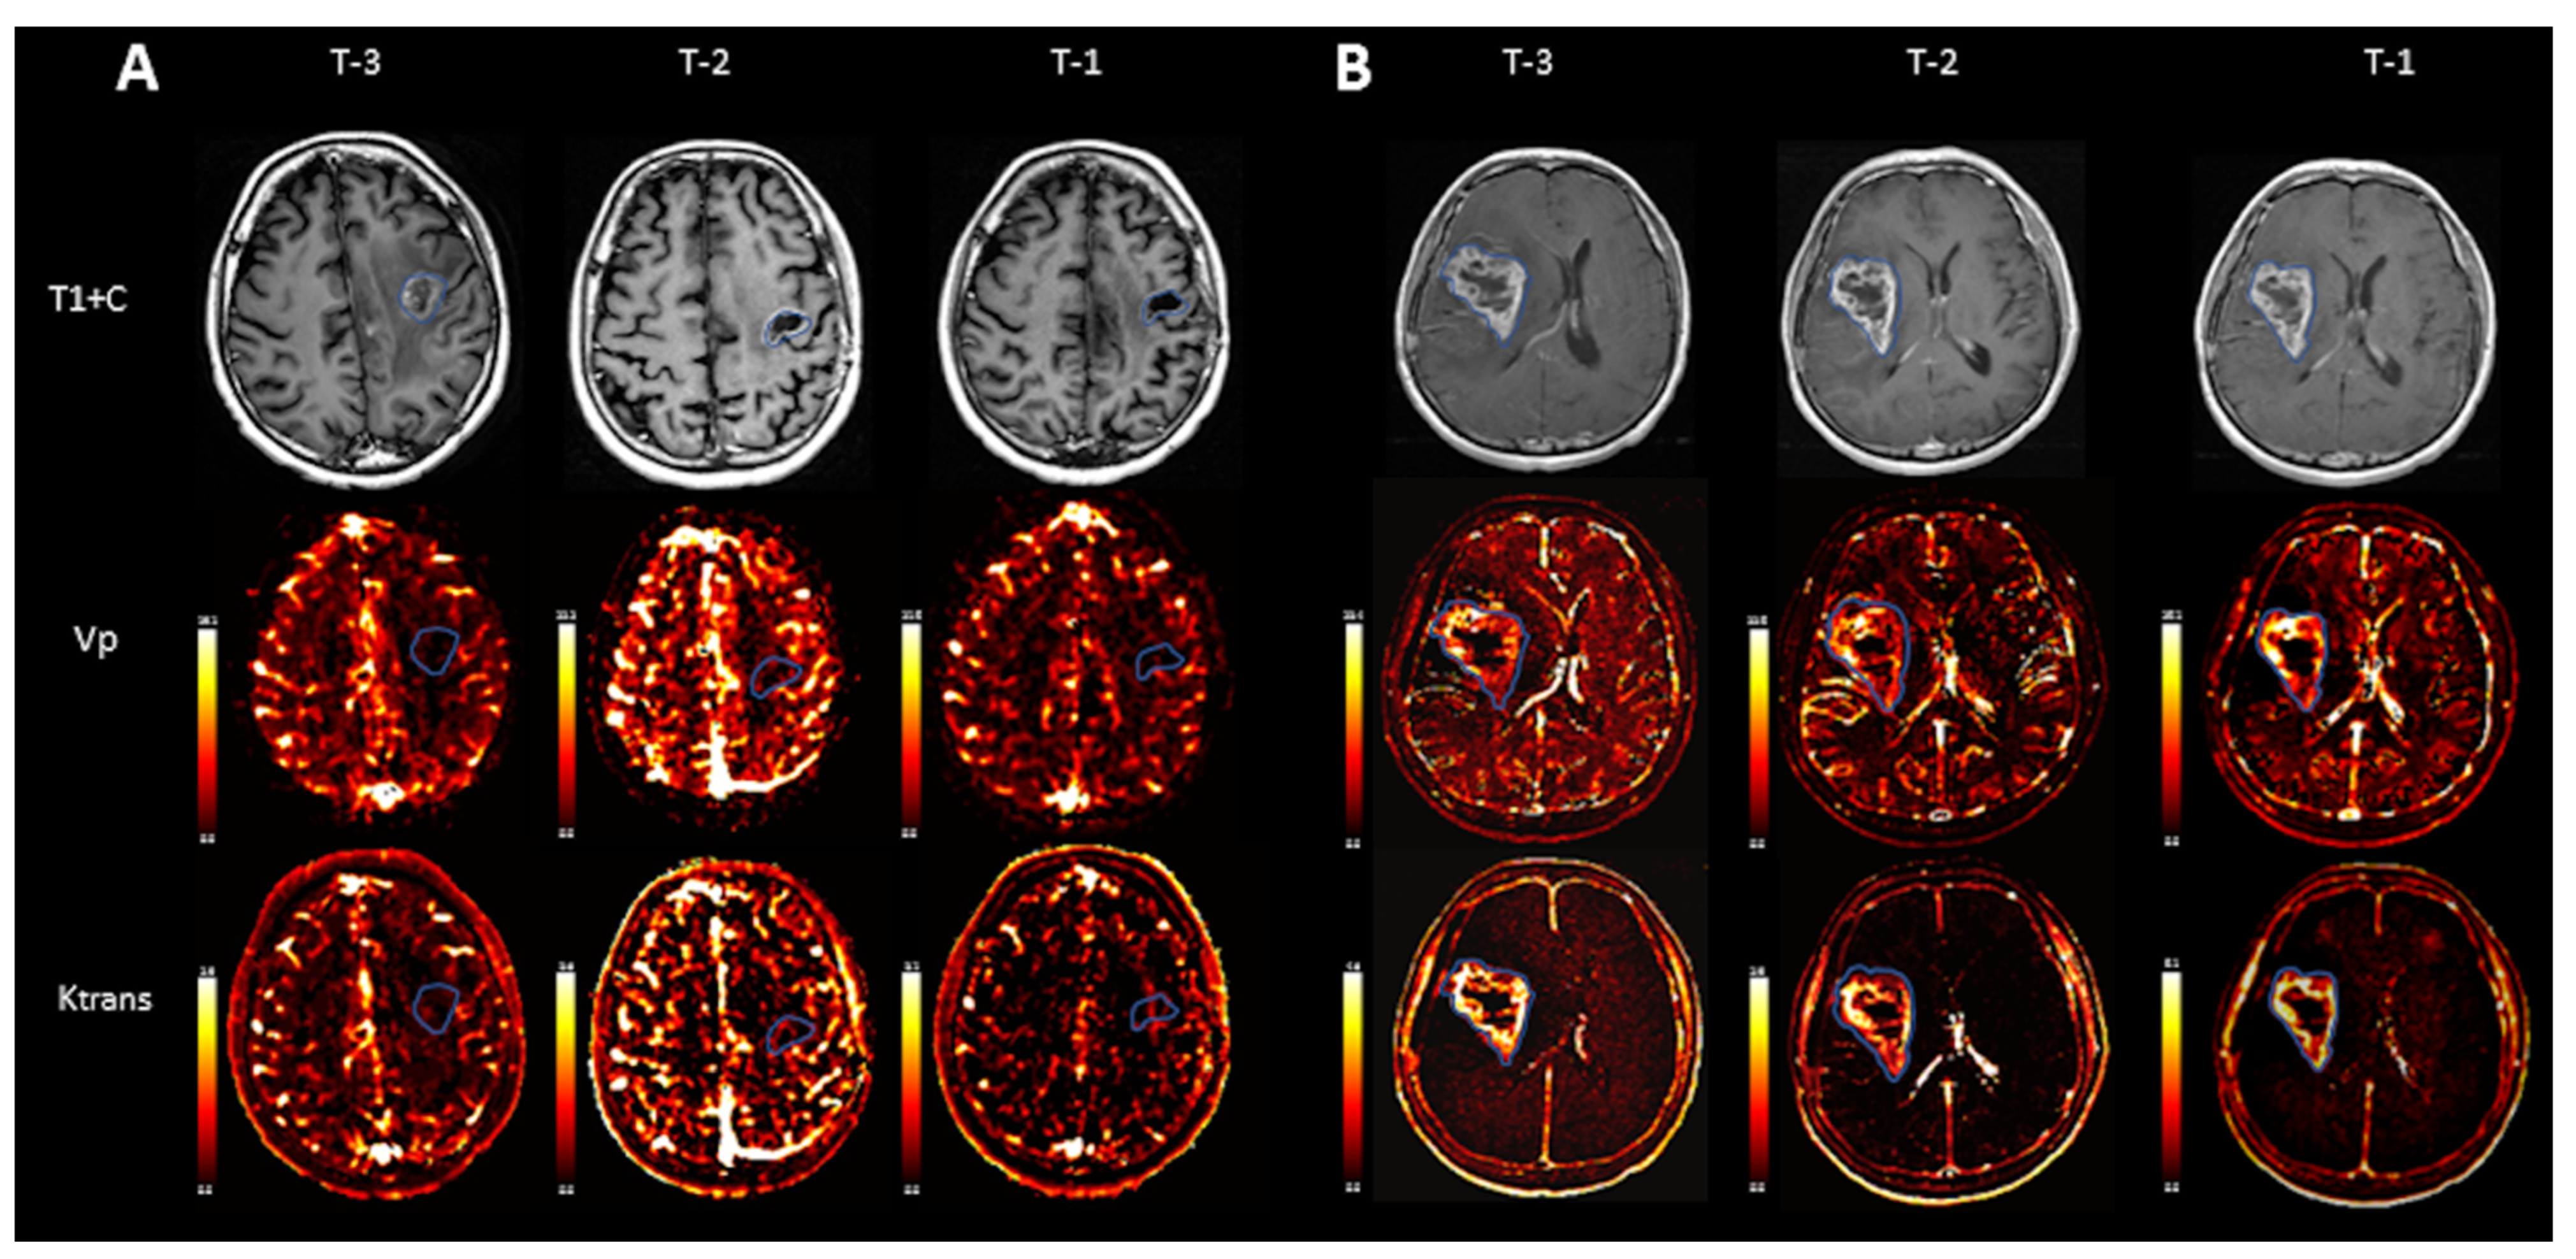

3.2. Conventional MRI Findings

3.3. Quantitative Perfusion Analysis